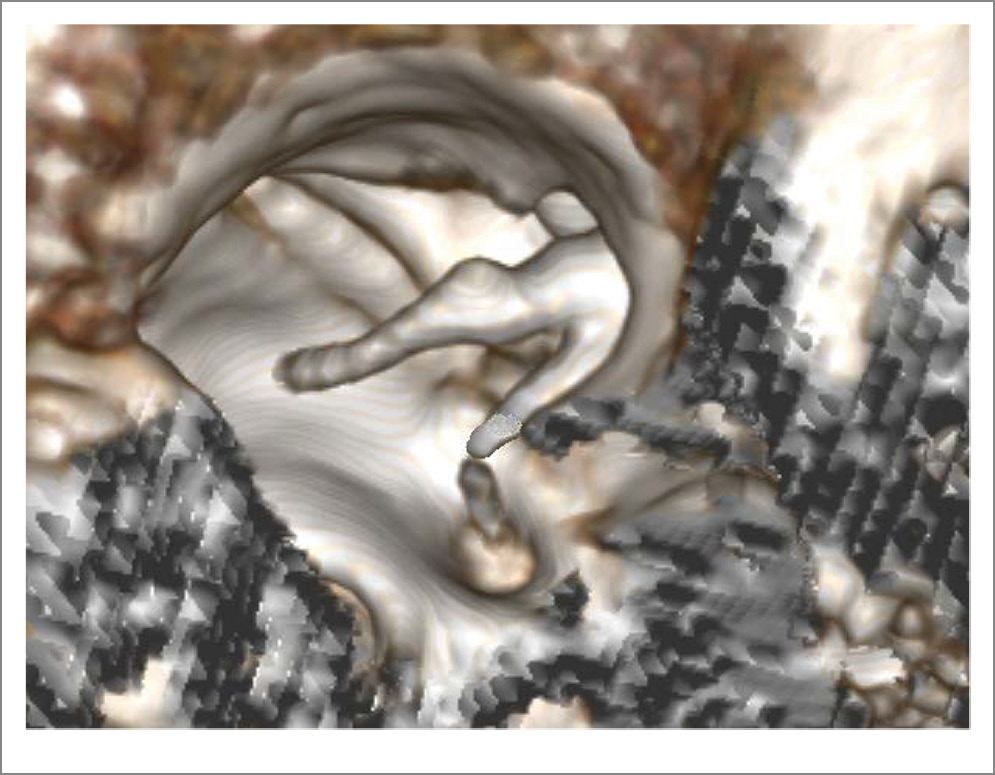

Virtual CT endoscopy is a good tool for the diagnosis of isolated congenital anomalies of the ME [19], which makes it possible to diagnose with great accuracy the presence of bone adhesions be-tween AOs and the TC structures, the breakdown of inter-ossicular connections and deviations from the normal configuration of the elements of the AO chain. In the diagnosis of gusher syndrome, this method, like multispiral CT (MSCT), can only indirectly indicate a possible increase in perilym-phatic pressure when based on the morphological changes in the IE structures, such as the fistula of the bone wall of the IAC, the dilation of the perilymphatic duct and the cochlear window.

In March 2023, patient L., 24 years old, presented at the St. Petersburg Research Institute of ENT with hearing loss in both ears, more on the left, and periodic mixed tinnitus. She had these symptoms for 2 years. According to the patient, she had no previous history of chronic or acute ear diseases; her family history is unremarkable. From 2010 to 2016, she was followed up by an epileptologist for an epilepsy episode; in 2016, she was withdrawn from the follow-up. Somatically, she had an arach-noid retrocerebellar cyst and a congenital anomaly of the urinary system, left kidney duplication. Other findings were unremarkable. The otoscopic pattern was normal. When conducting acoustic impedance measurement, the type A tympanogram on both sides was recorded; the stapedial reflex-es on both sides were absent. Tonal audiometry corresponded to a grade 2 mixed hearing loss on the left, with the Carhart notch at 2000 Hz and grade 1 conductive hearing loss on the right (Fig. 1). When examined with a 128 Hz tuning fork, the lateralization of sound in the Weber test spread to the left ear, the Rinne’s, Federicci’s and Gellé tests were negative on both sides. CT (Fig. 2, 3) and virtual CT endoscopy of the ME (Fig. 4) showed no changes in the ME and IE. The configuration of the semicircular canals, the vestibular aqueduct, and the perilymphatic duct were unremarkable. TB CT showed no demineralization of the labyrinth bone capsule, gross deformations of the AO chain, or abnormalities in the structure of the ME and IE.

Fig. 4. Virtual CT endoscopy of the TC. The normal configuration of the AO chain was visualized.